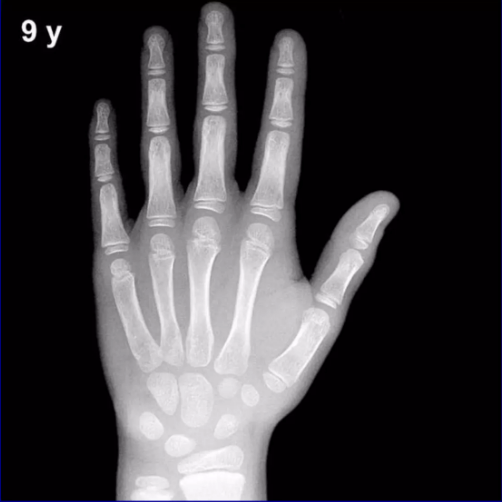

对孩子的手和手腕部X线检查,确定骨龄,判断骨骼是否生长过快。

△ 手和腕部X线检查测骨龄